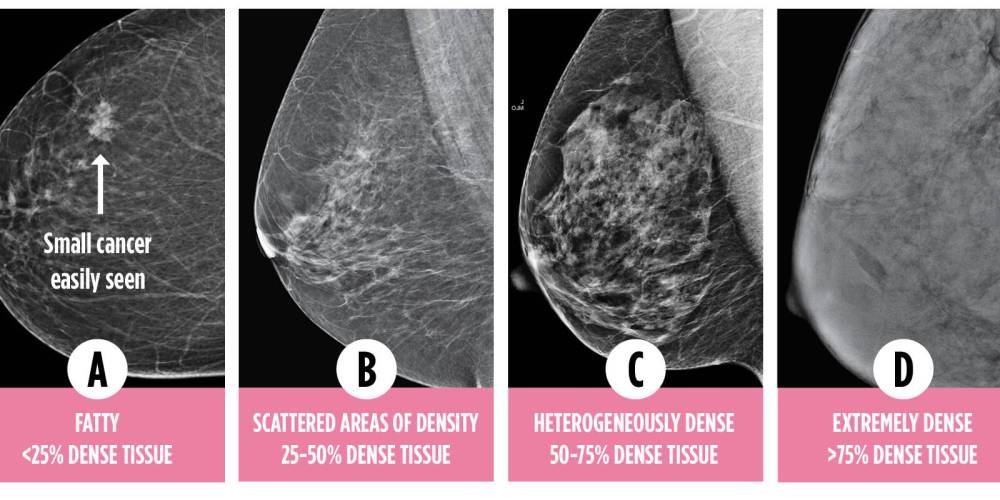

Breast density is divided into four categories: A, B, C and D. Those categories reflect the proportion of dense tissue relative to fat.

Dense Breasts Canada

Both cancer and dense breast tissue show up as white on mammogram screenings.

All women have fat and dense breast tissue in their breasts, but the amount varies. Only those in category C and D are classified as having dense breasts.

While mammography works exceptionally well in spotting cancer in women with fatty breasts, it alone is not enough for women who have dense breasts.

On a mammogram, a cancerous tumour and dense breast tissue both present as white, creating a masking effect in women with dense breasts.

In category D density, mammograms will miss about 40 per cent of breast cancers; in category C, about 25 per cent will be missed. Mammograms alone are not enough for women with dense breasts.